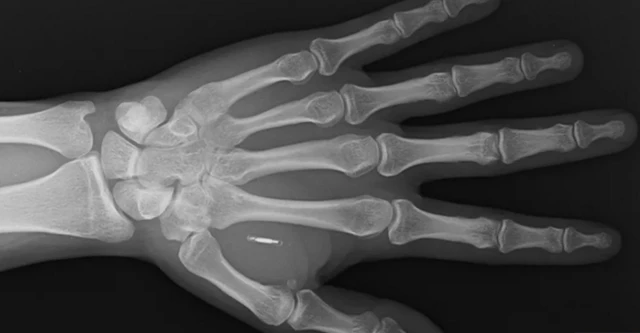

ኖላንድ የተገጠመለት ቺፕ ሳንቲም የሚያህል ነው። በአንጎሉ ውስጥ ያለውን የኒውሮን እንቅስቃሴ አንብቦ መልዕክቱን በራድዮ ሞገድ ያስተላልፋል።

አንደኛው፣ ገመድ አልባ እና በራድዮ ሞገድ መልዕክት የሚያስተላልፍ ቺፕ ነው። መጠኑ የሩዝ ፍሬ ያህላል። ለእያንዳንዱ ሰው መለያ ቁጥር ይሰጣል።

ሁለተኛው ዓይነት ቺፕ በተለይም ከጭንቅላት ኒውሮኖች ጫፍ ጋር ይገናኛል። መጠኑም ሳንቲም የሚያክል ነው። በአቅራቢያው ካለ ኮምፒውተር ጋር መረጃ ሊለዋወጥ ይችላል።